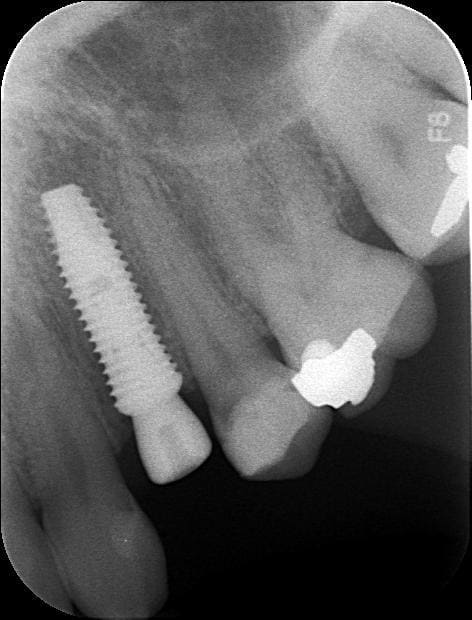

Pépélaratiche

23/12/2010 à 19h06

Oups

La toile résiduelle au niveau du col a l air qd même assez réduite sur le petit diamètre

Tu en penses quoi toi Pluton ???

Photo pluton1b h9n4ea - Eugenol

pluton

23/12/2010 à 19h15

que la radio ne met pas vraiment en valeur cet implant...

le filetage externe est assez peu marqué en fait

mais tu as raison...c'est un petit diamètre...3.4mm pour le fût et 3.6mm au col

expansion pour ce cas...j'aurais aimé pouvoir y glisser un 4mm...mais l'os me disait "stop" pour le 3.6 en 12mm

l'implant postérieur est un 4.5/8

maintenant, un ID en 3.7mm ou un dentium en 3.6...on doit être assez proche...niveau finesse au col...